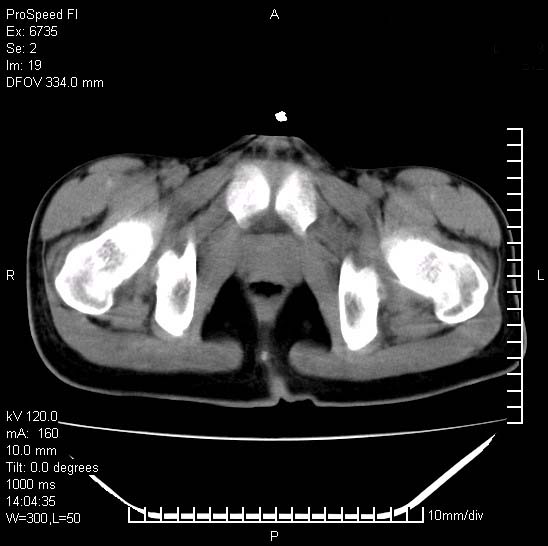

患者自诉胯部疼痛两年余,在当地服用中药,半月前至本院考虑骶髂关节结核,给予抗痨治疗。现发展至右下肢疼痛明显,活动受限,以膝关节处明显,拍膝关节平片无明显异常。

两侧骶骼关节改变,考虑强直性脊炎

左侧骶髂关节面限局性骨破坏,边缘硬化关节腔见钙化物;不出外tb

右侧骶髂关节也有类似改变,只是较左侧轻,首先考虑强直性脊柱炎,不除外结核,建议作hla-b27检查。

典型强脊炎改变,髋关节亦有累及

符合强直性脊柱炎表现。